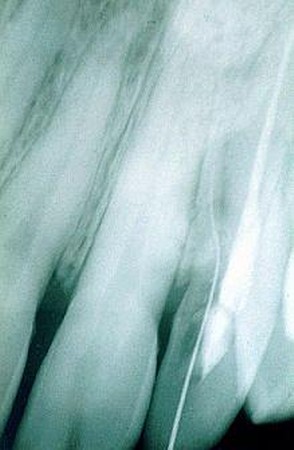

Orthopanthomografické (OPG) a intarorálne RTG snímkovanie je nevyhnutné pre stanovenie presnej diagnózy a plánu ošetrenia, pri preventívnych prehliadkach, ale aj pri bežnom ošetrení. Zobrazí už počiatočné kazy na miestach, ktoré nie sú na prvý pohľad viditeľné. Rovnako je dôležité aj pri endodoncii, teda pri ošetrení koreňových kanálikov, pri zápaloch nervu, pri paradentóze a kývavosti zubov, prípadne posúdení nutnosti extrakcie zuba.

V našej praxi sa pri diagnostike ochorení v dentoalveolárnej oblasti používa zobrazovacia technika, ktorá je neoddeliteľnou súčasťou vyšetrenia pacienta, ako aj následných ošetrení. Zhotovujeme digitálne intraorálne snímky. Ich výhodou je okamžité zobrazenie na monitore počítača, niekoľkonásobne znížená doba expozície, možnosť uloženia záznamu pre porovnanie do budúcnosti, možnosť aktívnej práce so snímkami, zobrazenie detailov, zmena kontrastu, farebné zobrazenie. Tieto snímky majú výrazný informatívny význam pri diagnostike tvrdých tkanív (zuby, kosti), závesný aparát zubov, pre plánovanie protetických prác, celkových sanácií, ale predovšetkým pri plánovaní implantačnej terapie.